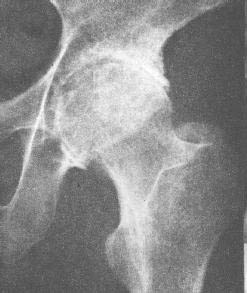

58岁女性,右髋不适,跛行月余。

先天髋关节发育不良,右侧关节囊积液

右侧股骨头缺血、坏死合并双侧关节腔积液。

髋关节类风湿性关节炎。关节间隙狭窄如细线状,股骨头和髋关节面均有多数小囊状凹陷,髋臼边缘唇样增生为继发退行性改变。

患者有明确类风湿关节炎病史,明确见其环指畸形尺侧偏。本例不象缺血性坏死,我努力往类风湿性关节炎靠,可是没发现典型病例可参考。

关节肿胀明显,关节间隙明显变窄,但骨质增生不多,是要考虑类风关,需与结核及骨性关节炎鉴别,髋臼前柱的囊变边缘光整,符合邻关节骨囊肿表现,但股骨头内囊肿边缘毛糙,应该是病变侵蚀所致,需进一步完善病史及相关检查鉴别

滑膜增生,关节腔积液,髂腰肌囊扩张,关节面软骨侵蚀破坏,间隙狭窄,股骨头变形,老年女性,有明确ra病史,符合ra关节炎,合并退变。

考虑右侧髋关节类风湿性关节炎并关节积液。

考虑右侧髋关节类风湿性关节炎并关节积液

滑膜增生,关节腔积液,髂腰肌囊扩张,关节面软骨侵蚀破坏,间隙狭窄,股骨头囊变,老年女性,有明确ra病史,符合ra关节炎,合并退变。支持!

结合病史符合类风湿性关节炎改变

髋关节类风湿性关节炎。